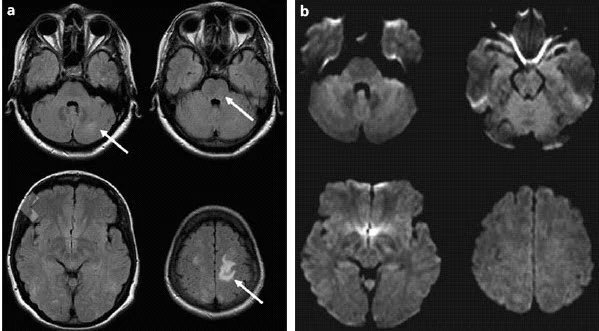

• CT and MRI show diffuse cerebral edema.